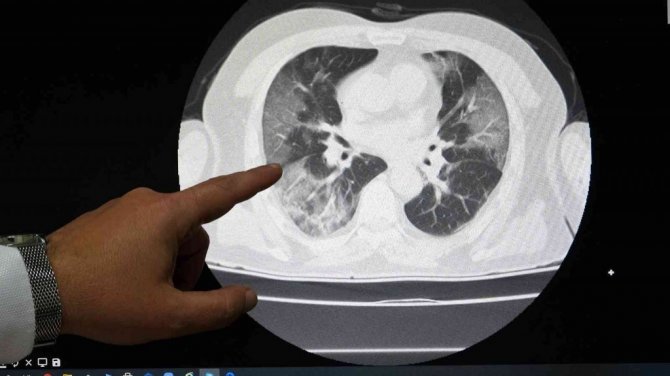

Göğüs Hastalıkları Uzmanı Doç. Dr. Ahmet Cemal Pazarlı, korona virüs yoğun bakım servisinde tedavi gören aşısız hastaların akciğer tomografisini sosyal medya hesabına paylaşarak, "Covid'in şakası yok. Aşısız vak'alarda akciğer tutulumu ve hastaneye yatışlar kaçınılmaz bir gerçek" mesajını verdi.

Tokat Gaziosmanpaşa Üniversitesi (TOGÜ) Sağlık Araştırma ve Uygulama Hastanesi korona virüs yoğun bakım servisinde yatan hastalardan yüzde 80'nden fazlasının aşısız olduğu bildirildi. Göğüs Hastalıkları Uzmanı Doç. Dr. Ahmet Cemal Pazarlı, son bir haftada yoğun bakım servisinde tedaviye alınan 7 korona virüs hastasının aşısız olduğuna dikkat çekti. Hastaların akciğer tomografi filmini sosyal medya hesabında paylaşan Pazarlı, "31 yaşında ek hastalığı olmayan bayan hasta, Covid'in şakası yok. Aşısız vak'alarda akciğer tutulumu ve hastaneye yatışlar kaçınılmaz bir gerçek. Geç olmadan aşılarınızı tamamlayın" mesajını verdi.